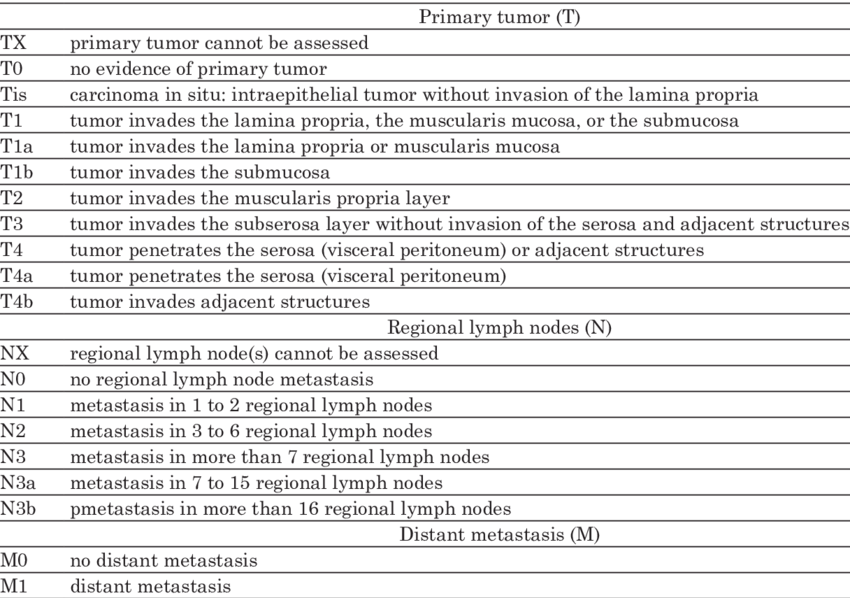

AJCC staging Gastric cancer